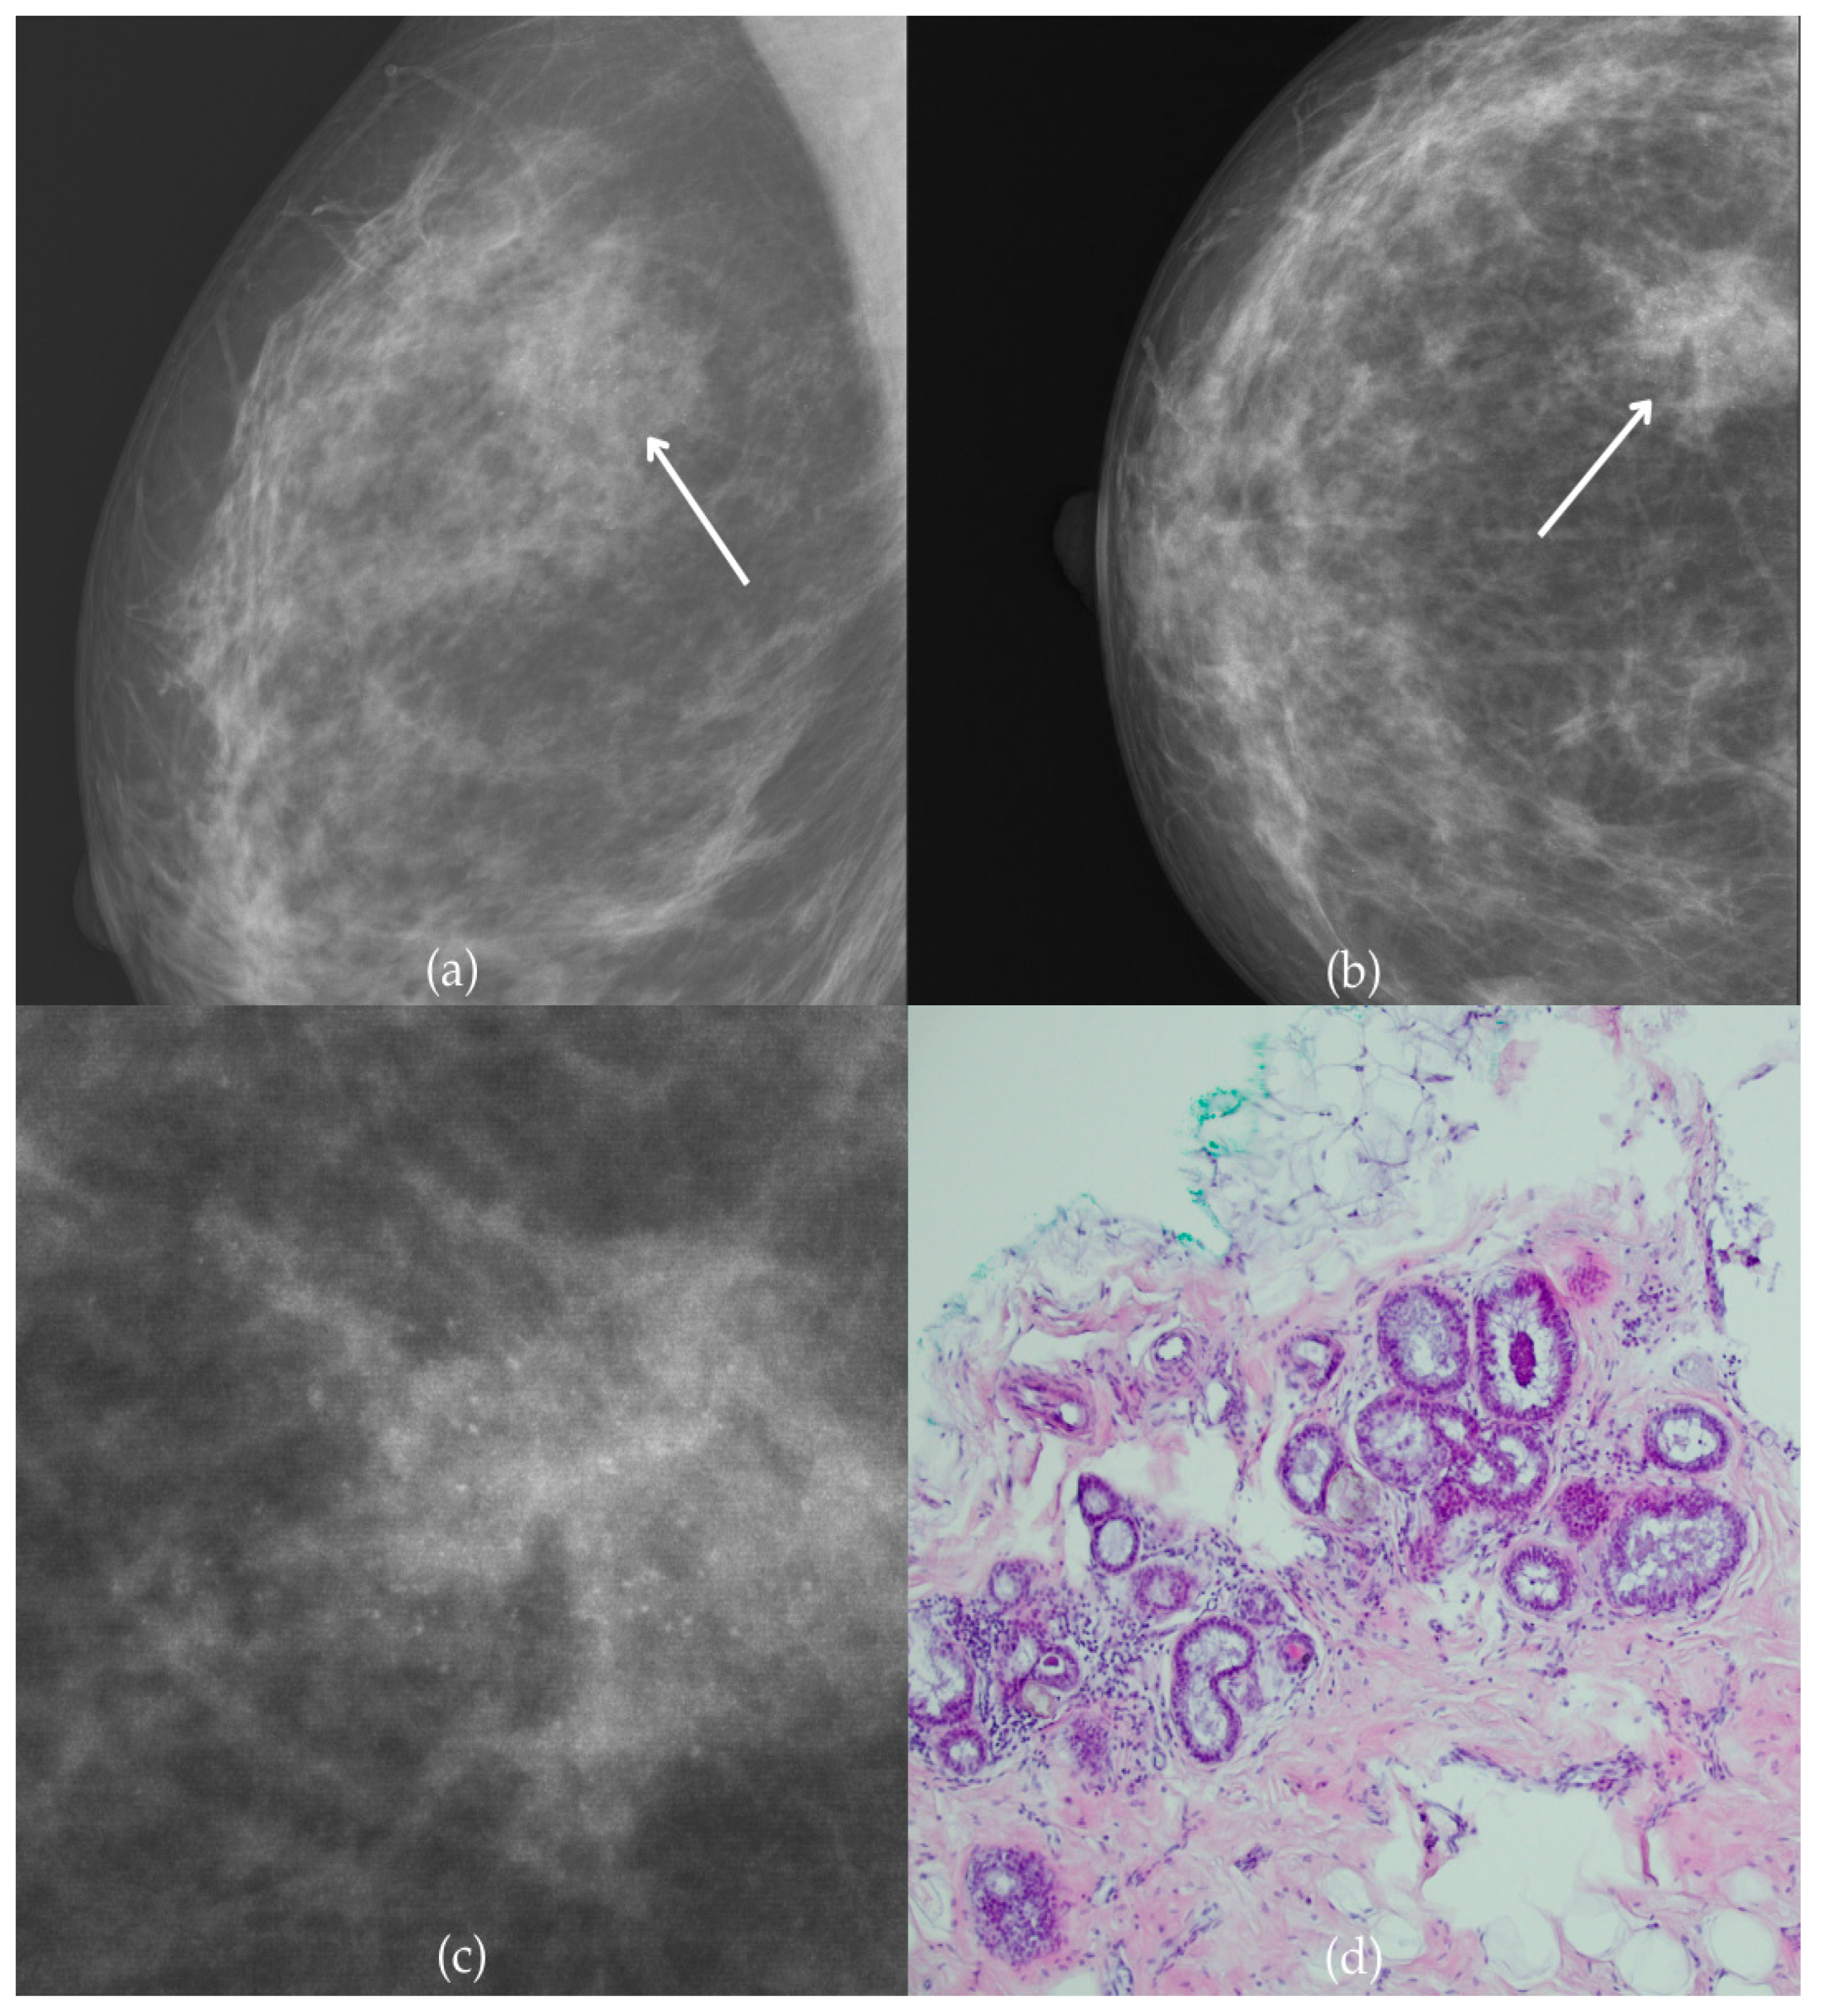

Figure 1 presents mammographic and histopathological images of a 74-year-old patient. The mammogram of the right breast shows grouped coarse heterogeneous and fine pleomorphic calcifications in the upper outer quadrant, classified as a BI-RADS 4 finding. Given the suspicious nature of these findings, a biopsy was performed. A tissue analysis confirmed the presence of a DCIS (category B5a). The patient underwent quadrantectomy, and the postoperative pathology confirmed the diagnosis. At the most recent follow-up, conducted one year after the initial diagnosis, the US examination was classified as BI-RADS 2, indicating benign findings.

Figure 1.

Ductal carcinoma in situ (DCIS). (a) Mediolateral oblique (MLO) mammography view; (b) craniocaudal (CC) mammography view of the right breast showing grouped coarse heterogeneous and fine pleomorphic calcifications (marked with arrows) in the upper outer quadrant. (c) Magnified mammographic image of grouped coarse heterogeneous and fine pleomorphic calcifications. (d) The histopathological image of the biopsy sample reveals the characteristic features of DCIS (HE staining; 40× magnification).